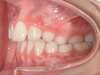

Cas 4 : Description

Chevauchement sévère. Traitement multibague sans extraction.

Avant

Après